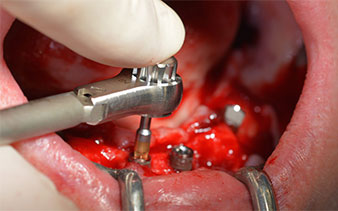

This corresponds to the next preset position in the Implantmed. Here we see the W&H contra-angle handpiece being held at a 45° angle to mesiocaudal in the region of 45 in order to preserve the mental nerve. The mental foramen is used as the anatomic reference for all drilling in this region. The subsequent holes were drilled at a reduced speed of 300 rpm (Fig. 10 and 11).

W&H contra-angle

Fig. 10

speed of 300 rpm

Fig. 11